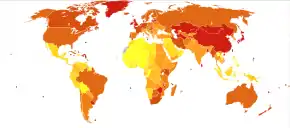

Esophageal cancer is the eighth-most frequently-diagnosed cancer worldwide,[2] and because of its poor prognosis, it is the sixth most-common cause of cancer-related deaths.[55] It caused about 400,000 deaths in 2012, accounting for about 5% of all cancer deaths (about 456,000 new cases were diagnosed, representing about 3% of all cancers).[2]

ESCC (esophageal squamous-cell carcinoma) comprises 60–70% of all cases of esophageal cancer worldwide, while EAC (esophageal adenocarcinoma) accounts for a further 20–30% (melanomas, leiomyosarcomas, carcinoids and lymphomas are less common types).[70] The incidence of the two main types of esophageal cancer varies greatly between different geographical areas.[71] In general, ESCC is more common in the developing world, and EAC is more common in the developed world.[2]

The worldwide incidence rate of ESCC in 2012 was 5.2 new cases per 100,000 person-years, with a male predominance (7.7 per 100,000 in men vs. 2.8 in women).[72] It was the common type in 90% of the countries studied.[72] ESCC is particularly frequent in the so-called "Asian esophageal cancer belt", an area that passes through northern China, southern Russia, north-eastern Iran, northern Afghanistan and eastern Turkey.[70] In 2012, about 80% of ESCC cases worldwide occurred in central and south-eastern Asia, and over half (53%) of all cases were in China.[72] The countries with the highest estimated national incidence rates were (in Asia) Mongolia and Turkmenistan and (in Africa) Malawi, Kenya and Uganda.[72] The problem of esophageal cancer has long been recognized in the eastern and southern parts of Sub-Saharan Africa, where ESCC appears to predominate.[73]

In Western countries, EAC has become the dominant form of the disease, following an increase in incidence over recent decades (in contrast to the incidence of ESCC, which has remained largely stable).[5][31] In 2012, the global incidence rate for EAC was 0.7 per 100,000 with a strong male predominance (1.1 per 100,000 in men vs. 0.3 in women). Areas with particularly high incidence rates include northern and western Europe, North America and Oceania. The countries with highest recorded rates were the UK, Netherlands, Ireland, Iceland and New Zealand.[72]